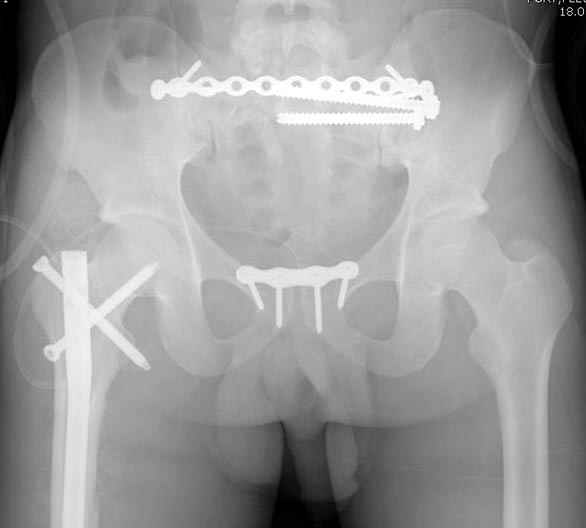

Здесь слайды случая больного с политравмой, включающей сегментарный перелом бедра и повреждение таза с нарушением тазового кольца, разрыв симфиза и перелома крестца зон 2 и 3.

На множественных слайдах важные моменты операции. Хотел бы подчеркнуть, как важно иметь возможности всех необходимых ренгенограмм, включая компютерную томографию и стандартных внутритазовых рентгенограмм (инлет и оутлет).